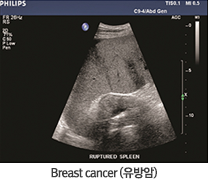

ÃÊÀ½ÆÄ¸¦ »ý¼ºÇϴ ŽÃËÀÚ¸¦ °Ë»ç ºÎÀ§¿¡ ¹ÐÂø½ÃÄÑ ÃÊÀ½ÆÄ¸¦ º¸³½ ´ÙÀ½ µÇµ¹¾Æ¿À´Â À½ÆÄ¸¦ ½Ç½Ã°£ ¿µ»óÈÇÏ´Â ¹æ½ÄÀ¸·Î °Ë»ç¸¦ ÁøÇàÇÕ´Ï´Ù.

µû¶ó¼ ÃÊÀ½ÆÄ °Ë»ç´Â °£ÆíÇϰí, ÀÎü¿¡ ÇØ°¡ ¾ø±â ¶§¹®¿¡ ¿µ»ó °Ë»ç Áß °¡Àå ±âÃʰ¡ µÇ´Â °Ë»ç¹ýÀÔ´Ï´Ù. ƯÈ÷ À¯¹æ, °©»ó¼±, ±Ù°ñ°Ý°ú °°ÀÌ ¿ì¸® ¸öÀÇ Ç¥¸é¿¡ À§Ä¡ÇÑ ±¸Á¶¸¦ ½±°í Á¤È®ÇÏ°Ô Æò°¡ÇÒ ¼ö ÀÖ°í, ÄÄÇ»ÅÍ ´ÜÃþÃÔ¿µ(CT), ÀÚ±â°ø¸í¿µ»ó(MRI)¿¡ ºñÇØ °Ë»ç Àåºñ¸¦ ½±°Ô ¿òÁ÷ÀÏ ¼ö ÀÖÀ¸¸ç ½ÇÁ¦ ¿òÁ÷ÀÌ´Â ±¸Á¶¹°À» º¼ ¼ö ÀÖ¾î, ÁßȯÀÚ³ª ¼ö¼ú Á÷ÈÄ È¯ÀÚÀÇ ÁßÀçÀû ½Ã¼ú¿¡µµ À¯¸®ÇÑ ÀåÁ¡ÀÌ ÀÖ½À´Ï´Ù.